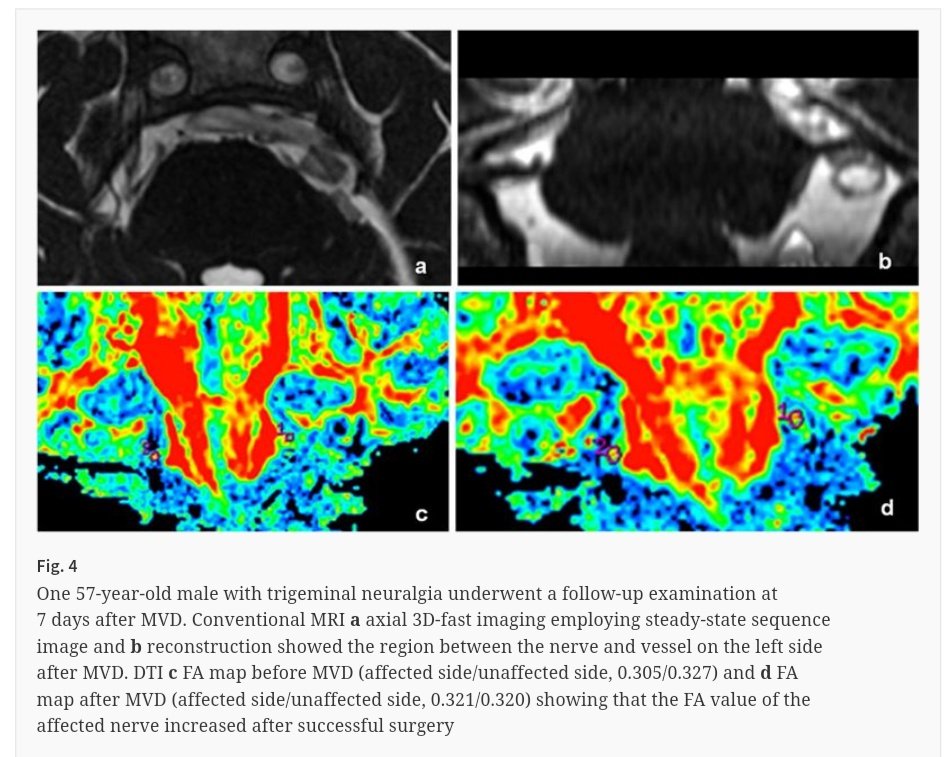

#EditorsChoice: #Diffusion tensor imaging of microstructural alterations in the #trigeminal nerve due to #neurovascular contact/compression #FreeToRead until 10 July #neurosurgery #nsgy #MVD #ActaNeuro bit.ly/313Seda

ActaNeuro's tweet image. #EditorsChoice: #Diffusion tensor imaging of microstructural alterations in the #trigeminal nerve due to #neurovascular contact/compression